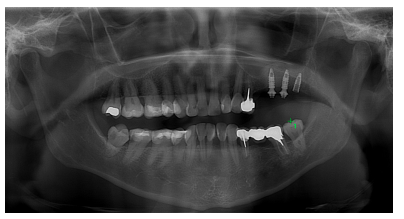

Se solicitó una radiografía panorámica con fines diagnósticos, evidenciándose la presencia de dos imágenes radiotransparentes, a nivel de 31 y sobre el 26. Sobre este último, se observó una lesión apical radiotransparente de forma ovalada de un tamaño de 10,68 mm de anchura y 9,80 mm de altura con límites bien definidos y contorno regular (Figura 1).

Tras estos hallazgos se aconsejó a la paciente la extracción del 26 conservando el 24. Una vez obtenido el consentimiento informado se procedió al corte de la prótesis, a nivel del 24 y posterior extracción del 26, sin complicaciones. Transcurridos cinco meses se volvió a solicitar un control radiográfico, en el que se observó la correcta remodelación de la zona, así como el déficit óseo para la rehabilitación con implantes (Figura 2).

A los tres meses, se solicitó un control radiográfico mediante radiografía panorámica observándose una correcta osteointegración de los implantes (Figura 13), por lo que se derivó a su prostodoncista para la rehabilitación de estos.